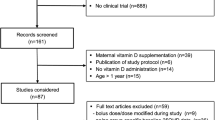

Abstract

Vitamin D has important roles in calcium metabolism and in the prevention of rickets and osteomalacia; low levels of 25-hydroxyvitamin D are common in the general population and amongst pregnant women. Whilst there is a wealth of observational evidence linking vitamin D deficiency to a wide range of disease outcomes, there are currently few high-quality randomised controlled trials to confirm any causal associations, although many are currently in progress. Furthermore, currently, the vast majority of published guidelines recommend standard supplemental vitamin D doses for children and pregnant women, yet there is increasing recognition that individual characteristics and genetic factors may influence the response to supplementation. As such, future research needs to concentrate on documenting definite beneficial clinical outcomes of vitamin D supplementation, and establishing personalised dosing schedules and demonstrating effective approaches to optimising initiation and adherence.

A number of national and international guidelines recommend vitamin D supplementation during childhood and pregnancy, mostly between 400 and 600 IU/day [134,135,136,137], although the Canadian Paediatric Society recommend up to 2000 IU/day during winter months [138]. However, there is evidence to suggest that in pregnancy this may be insufficient to achieve vitamin D replete status in many women. In the MAVIDOS study conducted in three centres in the UK at latitudes between 50.9 and 53.4°N, 83.3% of women randomised to 1000 IU/day cholecalciferol achieved a 25(OH)D > 50 nmol/l at 34 weeks gestation, compared with 35.6% of women in the placebo group. Moreover, in both treatment groups, the proportion of women who were vitamin D replete (> 50 nmol/l) in late pregnancy was lower in those who delivered in winter (December–May) (Fig. 4), highlighting that in the UK, 1000 IU/day cholecalciferol during pregnancy does not abolish seasonal variation in 25(OH)D status [15, 139]. Furthermore, in this study, women with 25(OH)D < 25 nmol/l at baseline were excluded from participation and therefore the true repletion rate across the general population would be expected to be lower than observed in the trial population. As such, if the aim of supplementation is to increase maternal 25(OH)D to > 50 nmol/l, then it is likely that 400 IU/day will not achieve this in many women. Similarly a study of children in Denmark (55°N) suggested a total vitamin D intake of 800 IU/day would be needed to maintain a serum 25(OH)D > 50 nmol/l in late winter [140]. However, whilst many observational studies do suggest that achieving higher 25(OH)D levels might have beneficial effects, such a change in public health policy should be based on established benefits in high-quality RCTs. It is also important to be certain that in addition to benefits, that a higher supplementation dose will not be harmful. Literature with regard to falls risk in older individuals suggests that moderate doses of vitamin D (600–1000 IU/day) may have a beneficial effect whilst high bolus doses increase the risk of falls [141]. Although antenatal supplementation with cholecalciferol doses up to 4000 IU/day and childhood supplementation with 800 IU/day did not result in hypercalcaemia or clinical side effects in clinical trial settings [80, 140], until a clear benefit of higher dose antenatal and childhood supplementation has been demonstrated, such doses should not be recommended.